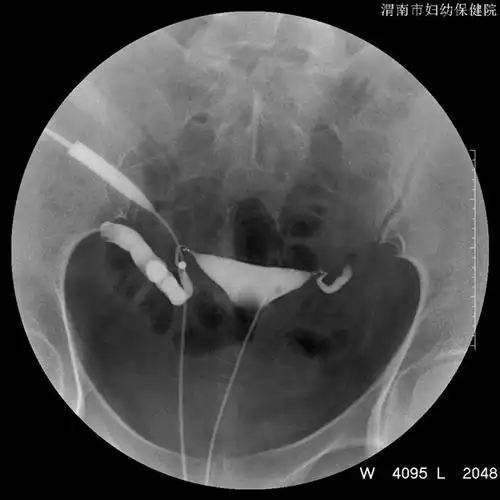

一张图看懂输卵管性不孕症,秒懂有木有

学会自己看输卵管造影片

子宫输卵管造影

各位同行帮我看一张子宫输卵管造影的片子是否有问题